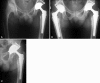

Methods: From a multiinstitutional trial, we reviewed 2408 patients with osteoarthritis implanted with 2601 prostheses of seven designs of a second-generation dual-mobility cup. The criteria for failure were migration, widening radiolucencies in any zone of the interface, or revision for cup loosening. The minimum followup was 5 years (mean, 7.7 years; range, 5-11 years).

Results: The 8-year survival rate of press-fit, grit-blasted cups was lower than that for press-fit, grit-blasted cups fixed with screws (91% versus 100%) and for tripod fixation (98%). The 8-year survival rate of press-fit, grit-blasted cups was less than that for press-fit, porous-coated cups made of the same alloy (91% versus 95%).

Conclusions: The data suggested primary fixation of grit-blasted dual-mobility cups should be secured with screws. Porous coating sintered on the convex side improved midterm survivorship. No deleterious effect of metallosis resulted from sintered titanium beads on stainless steel. Long-term followup is required to confirm these findings.